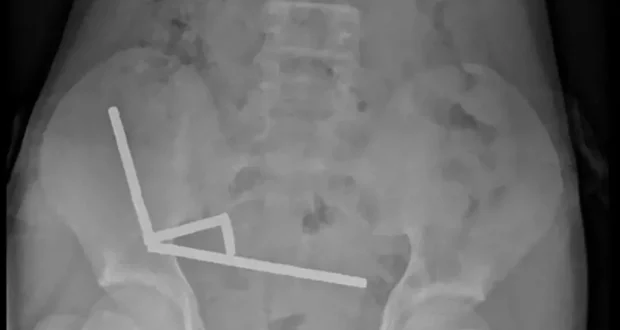

وأظهرت الأشعة أن المغناطيسات تكتلت معاً في 4 خطوط مستقيمة داخل أمعاء المراهق، و”يبدو أنها كانت في أجزاء منفصلة من الأمعاء ملتصقة ببعضها البعض بسبب القوى المغناطيسية”، وفق الأطباء.